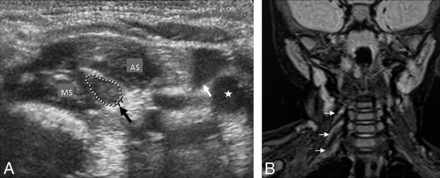

All patients had PST on the affected side with no detectable pre-GI on US (Figs 1 and 2). The PST appeared as a smooth well-defined solid mass that usually extended laterally to the BP trunk region on US, with no internal vascularity. The echogenicity of PST (90%, 114/127) was usually similar to that of the scalene muscles, but some lesions had mixed echotexture (10%, 13/127). US revealed 127 PSTs that showed the affected number of nerve roots in 55 patients. The mean caliber of the PST was 6.6 ± 1.9 mm (range, 3.4–10.2 mm), and the thickness of the PST was not significantly different among the Narakas groups (P = .26) and between US and MR imaging examination (6.1 ± 2 mm [range, 3–11.6 mm]), (P = .34). Although the thickness of all PSTs was reduced in the follow-up period (at first evaluation, 6.3 ± 1.8 mm, [range, 3.3–9.6 mm], at the second evaluation, 6.1 ± 1.7 mm [range 3.1–9.3 mm]), PSTs remained persistent thereafter. All PSTs also did not show cystic/hemorrhagic degeneration or calcification on follow-up.

Case 25, in a 1-month-old infant with right-sided total brachial plexus paralysis with homogeneous periscalene soft tissue at the C5–7 level (arrow) between the anterior (AS) and middle scalene (MS) muscles on a transverse sonographic image (A). The thin arrow and star show the right internal jugular vein and carotid artery, respectively, on image A. B, The transverse scan sonographic image shows the normal interscalene space (black arrow) and nerve roots as hypoechoic oval cross-sections (white arrows) between the AS and MS muscles. The thin arrow and star show left internal jugular vein and carotid artery, respectively, on B. C, Coronal oblique fat-suppressed TSE T2WI shows periscalene soft tissues (arrows) coursing through the right interscalene space at the C5–7 level, findings similar to those in A.

Case 20, a 2-month-old female patient with a right brachial plexus birth injury. A, Transverse scan sonography of the interscalene space shows homogeneous echogenicity periscalene soft tissue with fusiform morphology (black arrow) between the anterior (AS) and middle scalene (MS) muscles at the C4–7 level. The white arrow and star show the right internal jugular vein and carotid artery, respectively. B, Coronal oblique fat-suppressed TSE T2WI shows periscalene soft tissues (arrows) coursing through the right interscalene space at the C4–7 level, findings similar to those in A.

All patients had abnormal MR imaging findings on the affected side. The nerve root avulsion/retraction was seen in 43 patients in at least 1 level (n = 25) on MR imaging, and root avulsion without associated pseudomeningocele was seen in 4 patients (Fig 3A). The surgical electrophysiologic examination did not confirm the root avulsion diagnosis in 2 patients with a positive MR imaging finding, case 5 (C5) and case 49 (C5 and C6), and it revealed avulsion in 3 patients with negative MR imaging findings, cases 37 and 45 (C7, C8, and T1) and case 52 (C5). In clinical terms, there were also discrepancies between clinical findings and MR imaging in these patients (cases 5, 37, 45, 49, and 52). The pseudomeningocele without associated root avulsion was seen in 3 patients (cases 33, 39, and 42), and nerve root avulsion in the pseudomeningocele was not evaluated optimally in 3 patients (cases 5, 37, and 45) (Fig 3B). MR imaging showed 139 PSTs that usually showed signal similar to that of scalene muscles (93%, 129/139) on T1WI and higher signal (100%, 139/139) than muscles on T2WI. The locations and extensions of the PST were similar to those of US findings. The US and MR imaging showed concordance in 85% (47/55) of patients with PST (91%, 127/139) except in 8 cases (C8 [n = 4] and T1 [n = 8]) (Figs 1C and 2B). The clinical, US, and MR imaging findings were concordant in 85% of patients (47/55) with post-GI.